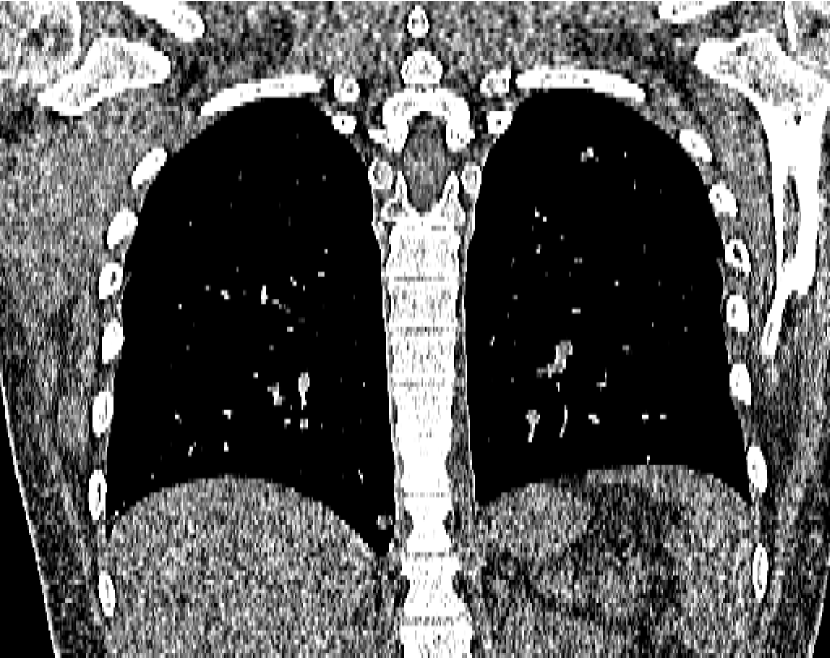

Figure 14: Qualitative clinical results from a thoracic CT staging dataset for a 12-year-old with osteosarcoma with pulmonary metastases. The clinical standard hybrid IR is shown on the left and JENG is on the right. (a) The clinical standard hybrid IR in lung window with a window center of -600 HU and a window width of 1500 HU. (b) JENG at a resolution comparable to the clinical standard, but with less noise and fewer artifacts. (c) The clinical standard hybrid IR in soft tissue window with a window center of 55 HU and a window width of 440 HU. A metastatic lung cancer nodule can be found in the left upper lobe. (d) JENG in soft tissue window at a comparable resolution, but with less noise and fewer artifacts. Note that JENG is not fully corrected for beam hardening artifacts.

Figure 15: An example cross-plane image from the same thoracic dataset as in Fig. 14. (a) A coronal-view image slice of the clinical standard hybrid IR in soft tissue window. (b) JENG at a comparable resolution but with reduced image noise and artifacts.